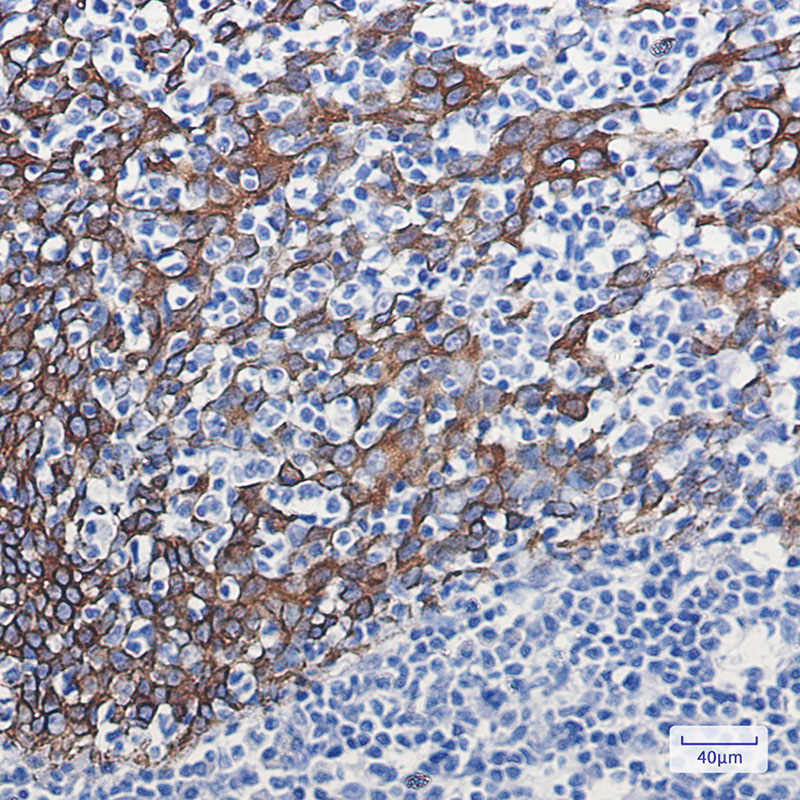

Product Image

IHC | 1/50-1/100 |

K16 a type I cytoskeletal keratin. The keratins are intermediate filament proteins responsible for the structural integrity of epithelial cells and are subdivided into cytokeratins and hair keratins. There are two types of cytoskeletal and microfibrillar keratin: type I (acidic; 40-55 kDa) [K9 to K20] and type II (neutral to basic; 56-70 kDa) [K1 to K8]. |